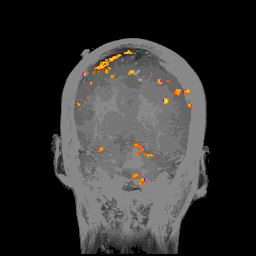

脑电图已经拥有接近一个世纪的历史,这种技术就是在脑袋上贴一堆电极:

一种完全非侵入性的脑机接口工具,脑电图可以记录下大脑中不同区域的电流活动,然后生成这样的结果: